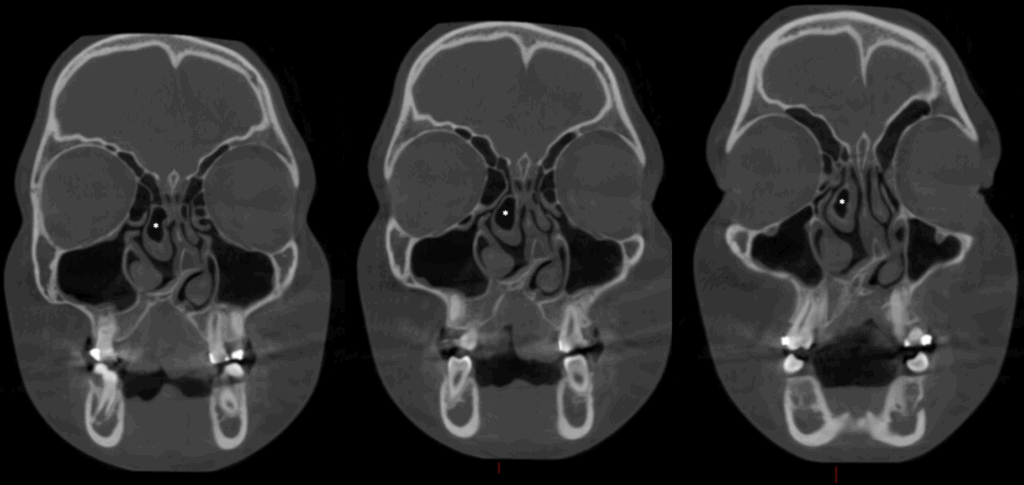

En la radiografía panorámica (Figura 1), se observa neumatización de senos maxilares, defecto óseo en zona anterior izquierda de maxilar superior, ausencia de piezas 22 y 23; además de la aparatología ortodóntica en piezas del maxilar superior.

Radiografia Panorámica